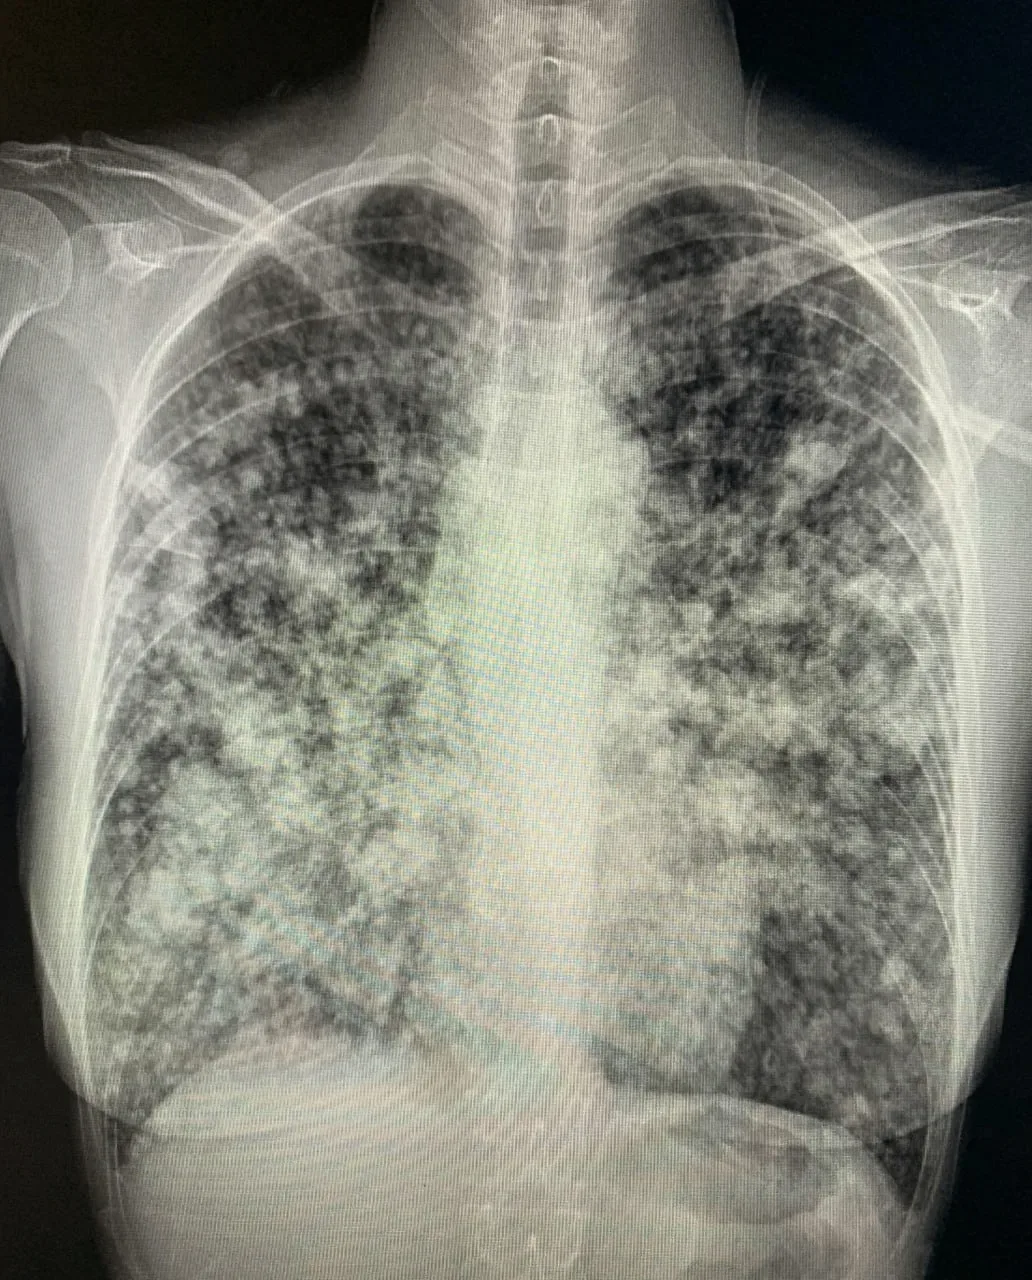

В России зумеры массово попадают в больницы от вейпа Попкорновая болезнь накрывает вейперов России. За последний год число заболевших выросло на 30%. Пульмонологи фиксируют резкий рост тяжёлых заболеваний лёгких среди подростков и молодёжи до 35 лет, которые на регулярной основе курят электронные сигареты. Всё дело в веществе 2,3-бутандионе. Раньше это вещество добавляли только в вейпы с ТГК, чтобы создавать определённый вкус попкорна, но недавно русские производители жижи стали добавлять это вещество во все фруктовые вкусы для создания яркости. Изменения лёгких при вдыхании фатальны. Сначала…